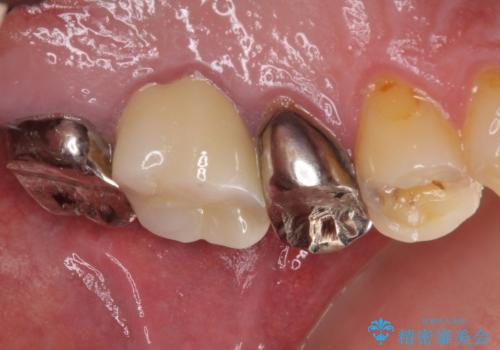

根管治療を行い、その後フルジルコニアクラウンにて補綴することとしました。

治療後すぐに痛みが引き、治療後半年が経過した際のレントゲン写真では、排膿の元となっていた、歯根先端の病変の消失が認められました。